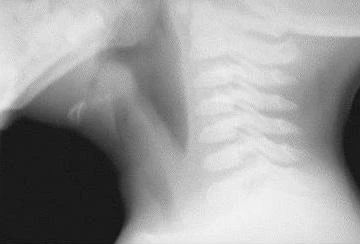

Soft-tissue lateral neck radiograph reveals edema of epiglottis consistent with acute epiglottitis. (https://emedicine.medscape.com/article/763612-overview)